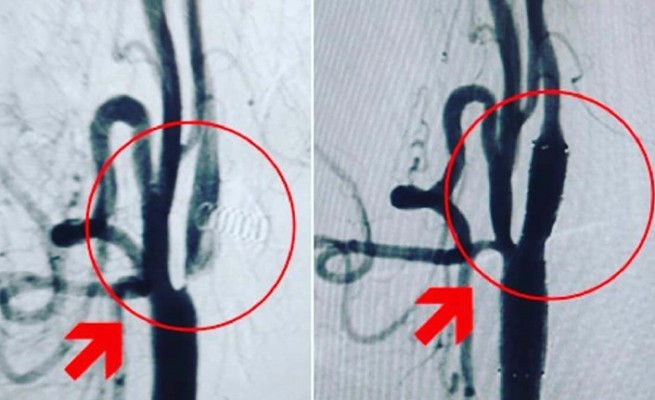

Burada yapılan ilk müdahalenin ardından hastayı muayane eden ve tetkikler yapan Doktor Sedat Yaşin, hastanın sol şah damarında yüzde 99 darlık, sol beyin damarında ise tam tıkanıklık tespit etti.

Teşhisin ardından alınan kararla yapılan operasyonlarda, hastanın beyin damarındaki pıhtı alınırken, sol şah damarındaki darlık ise takılan stentle açıldı.